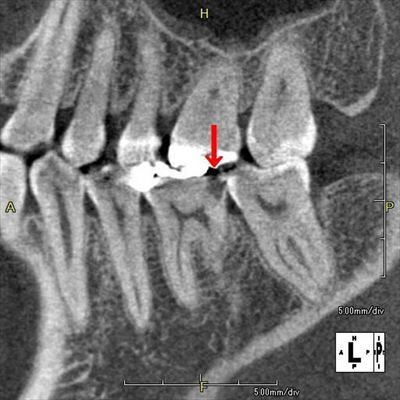

右下第一大臼歯の遠心隣接面がむし歯になっていることがCTの断面像から判ります(赤矢印)。

歯頸部付近から歯冠部にかけて水平断面の連続画像です。

むし歯になっている部分が黒くなっています。